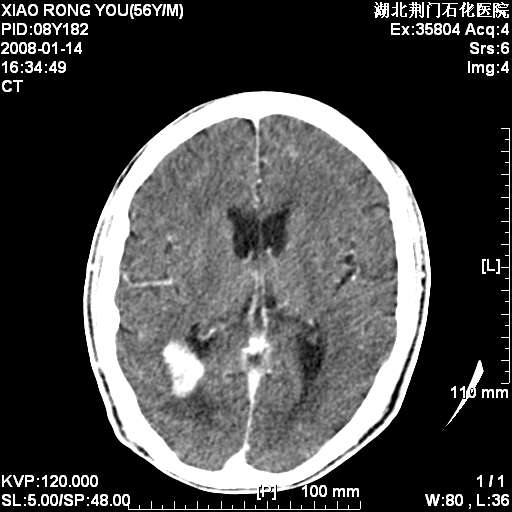

1月后复查

多发,考虑转移

转移瘤,前后对比可发现复查片左顶叶出现一低密度灶

病变范围在一个多月时间增大,且密度不均周围有税种,并且多发!考虑转移瘤!

左枕/顶叶出现新病灶,转移瘤

强化明显,周围水肿轻,考虑脑膜瘤

周围水肿不明显,增强后明显强化,应该多脑膜瘤或着血管瘤。